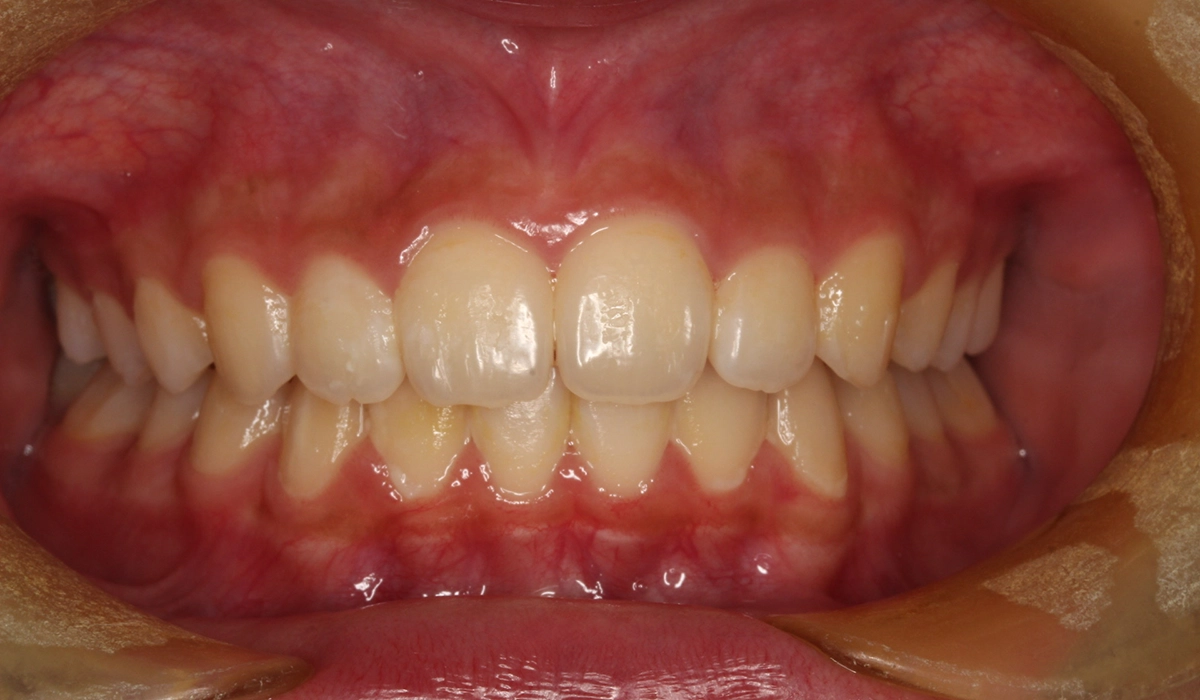

術前:正面

術後:正面